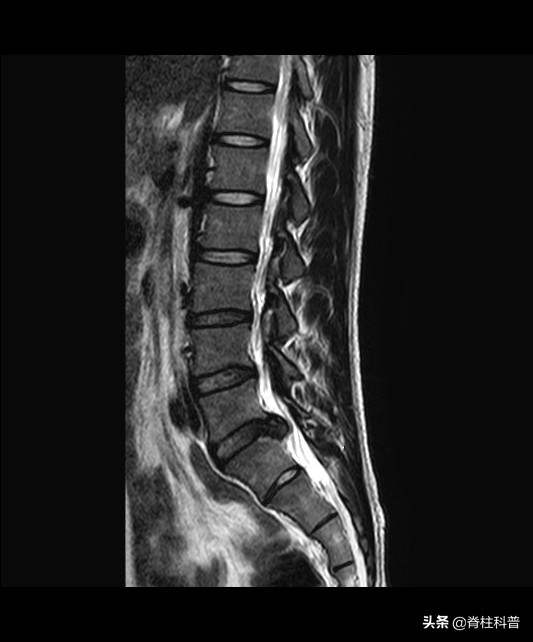

核磁共振在观察突出物的形态和与其他结构的关系中最清晰!

在腰椎核磁共振的扫描中,能够观察到椎间盘的脱出、突出、膨出、变形等不同时期的病理变化,还可以通过多节段连续成像、三维切面,观察突出物和后纵韧带、纤维环、椎间盘、脊髓、马尾神经、椎弓之间的关系。尤其是硬膜囊神经根和突出物的关系,由此推断出髓核的变化,以及周围组织粘连、出血、水肿等结构上的变化。

虽然MRI扫描的时间较长,价格在三项检查中价格最高,但没有放射性,具有较高的安全性。而且能够通过全方位、多序列成像,更好的观察病变位置的状况,还能清晰的观察到软组织的状况,避免腰椎结构有叠影,以便提高诊断的准确率。不过,受检查仪器的局限,身体内带有金属的患者、患有幽闭恐惧症的患者,均不适合进行核磁共振检查。

核磁共振片子